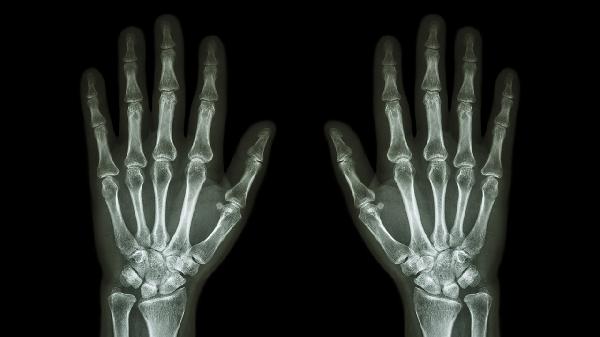

左手大拇指关节疼痛怎么治疗

左手大拇指关节疼痛可通过热敷、制动休息、药物治疗、物理治疗、手术治疗等方式缓解。该症状可能与外伤、骨关节炎、腱鞘炎、痛风性关节炎、类风湿关节炎等因素有关。